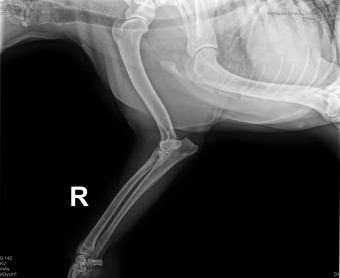

CASSANDRA VON KONIGS-TERRY

( CASSY )

Data nasterii:

14.11.2024

FOCK RODICA si VALCOVICI ION